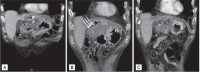

A 71-year-old male patient was readmitted to our hospital 1 month after discharge because of relapse of abdominal pain. He had been diagnosed with hepatocellular carcinoma (HCC) 1 year prior and had undergone repeated transcatheter arterial chemoembolization and radiotherapy. During the last hospitalization, he was diagnosed with a liver abscess complicated by previous treatments for HCC and was treated with intravenous antibiotics and abscess aspiration. Follow-up abdominal computed tomography revealed a liver abscess with a duodenal fistula, which was successfully treated with endoscopic Histoacryl injection into the fistula. Liver abscesses with duodenal fistulas rarely occur, but they are intractable and possibly fatal in patients with HCC. In the literature, they have frequently been managed only with abscess treatment without fistula management. We herein report the first case of a patient with a liver abscess complicated by a fistula between the duodenum and the abscess, which was treated with endoscopic Histoacryl injection.